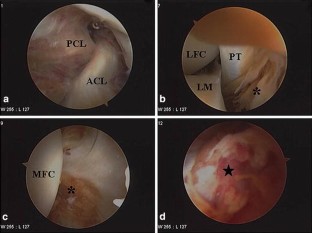

This study reports a case of unusual vascular complication related to the staple fixation for the tibial avulsion fracture of the posterior cruciate ligament (PCL). The patient, who experienced recurrent hemarthrosis 12 months after staple fixation for the avulsion fracture of the PCL, was successfully managed by removing the staple and suturing the bleeding focus of the popliteal artery. Injury to the popliteal artery by the prominent staples could be the culprit causing the recurrent hemarthrosis. This type of delayed popliteal artery injury should be kept in mind in open reduction and internal fixation for the tibial avulsion fracture of the PCL.

Fig. 3